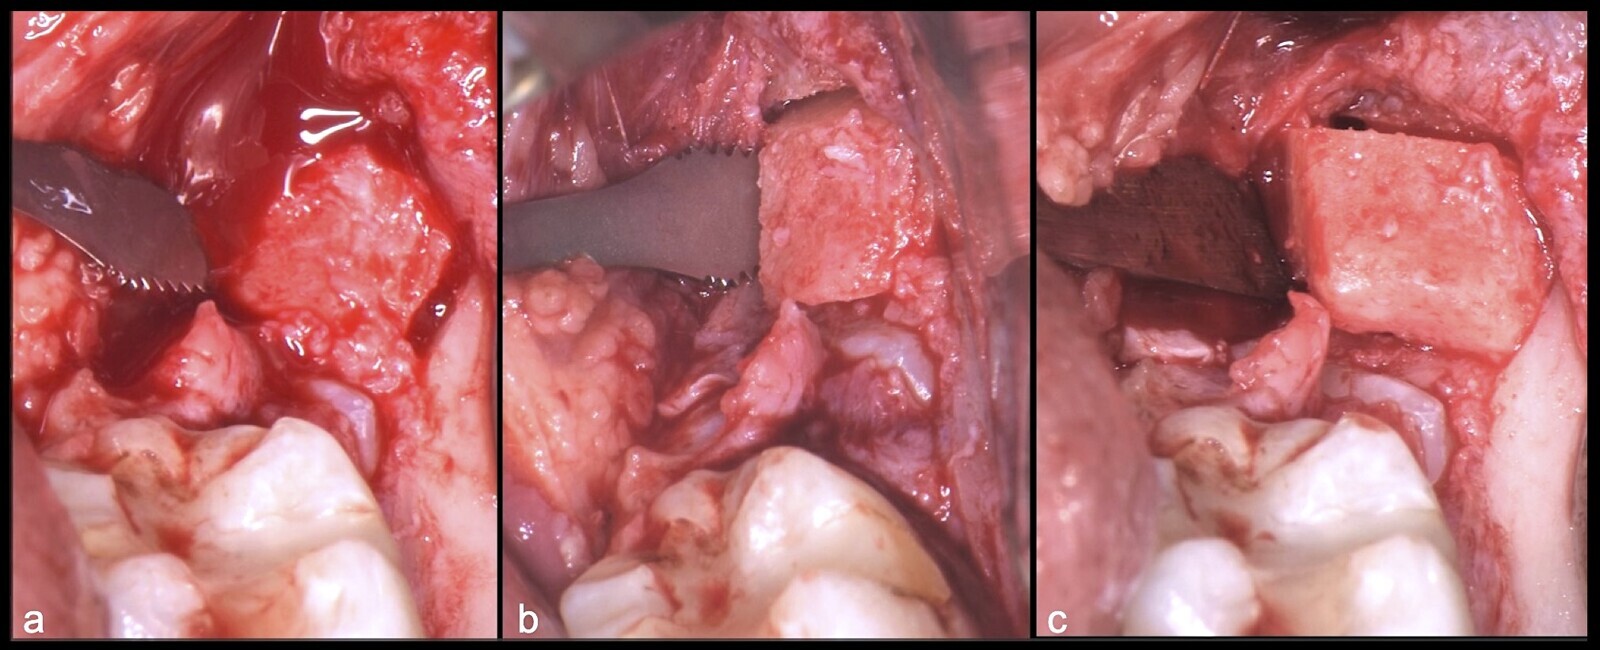

Figura 17. Osteotomía con el inserto plano de corte de punta aserrada del piezoeléctrico (a, b). Demarcarción de los límites de la ostectomía del fragmento óseo (c).

Figura 18. Finalización de la osteotomía del primer fragmento óseo con inserto plano de corte de punta aserrada del piezoeléctrico (a, b, c).

Figura 19. Retiro del primer fragmento óseo (a, b). Extirpación del segundo bloque óseo con el inserto plano de corte de punta aserrada (c).